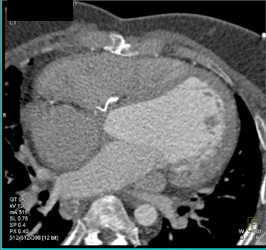

Type A Dissection